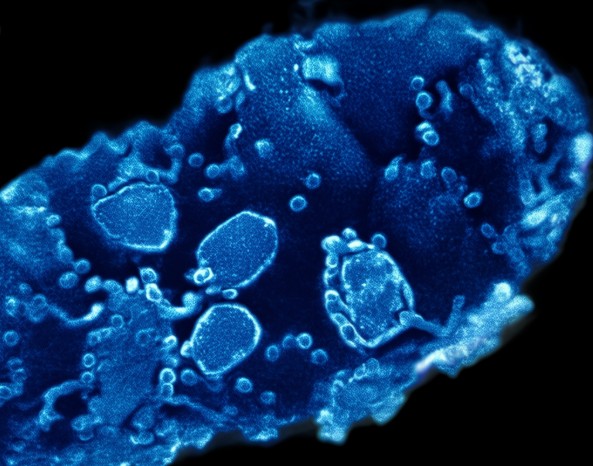

6. 角膜内皮检查

用途:评估内皮细胞的数量、形态和功能状态

方法:使用非接触角膜内皮显微镜检查

特点:快速、无痛、不接触眼球,特别适合儿童和紧张患者

3. 评估角膜内皮功能

评估内皮细胞数量(正常范围:30岁前约3000-4000个/mm²;50岁左右约2600-2800个/mm²)

评估细胞形态是否规则(是否为规则六角形)

预测角膜水肿和失代偿风险(细胞密度<800个/mm²时风险显著增加)